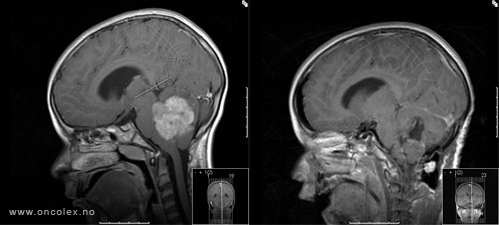

MR-bilder av 14 år gammel gutt med pilocytisk astrocytom før- og etter fjerning av svulst